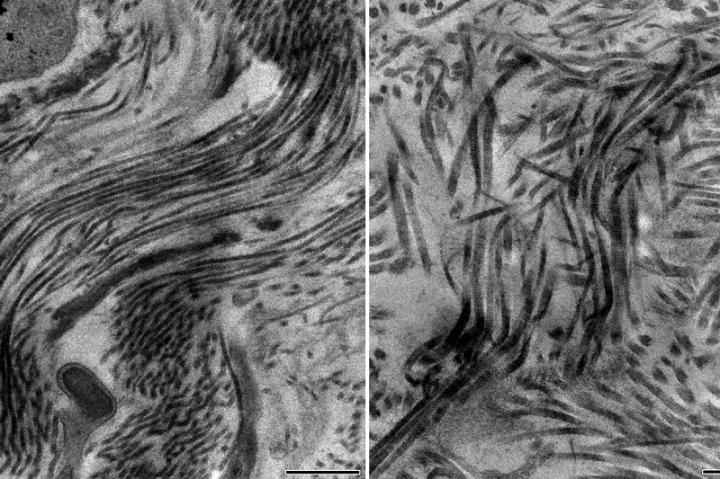

Healthy Scar with Collagen Type 5; Unhealthy Scar without Collagen Type 5

image: Electron microscopy images showing a healthy scar containing collagen type 5 with scar fibers smoothly arranged in parallel (left) and unhealthy scar containing no collagen type 5 with a disorganized architecture with disarray of scar fibers (right). view more

Credit: Cell/UCLA Broad Stem Cell Research Center